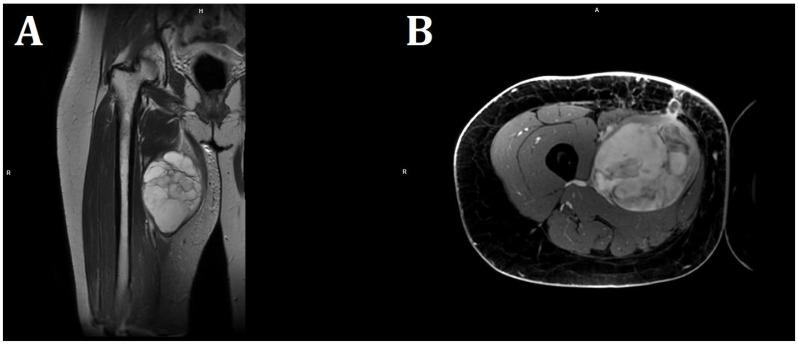

We report the case of a 36-year-old female patient on the 11th day of the puerperium after a cesarean section. The patient presented to the gynecology ward owing to the sudden appearance of a tumor in the medial part of her right thigh. The lesion was non-painful, mobile, soft, approximately 20 cm in diameter, and protruded above the level of the rest of the thigh surface. A suspicion of hematoma was raised. The final diagnosis was high-grade MLPS.